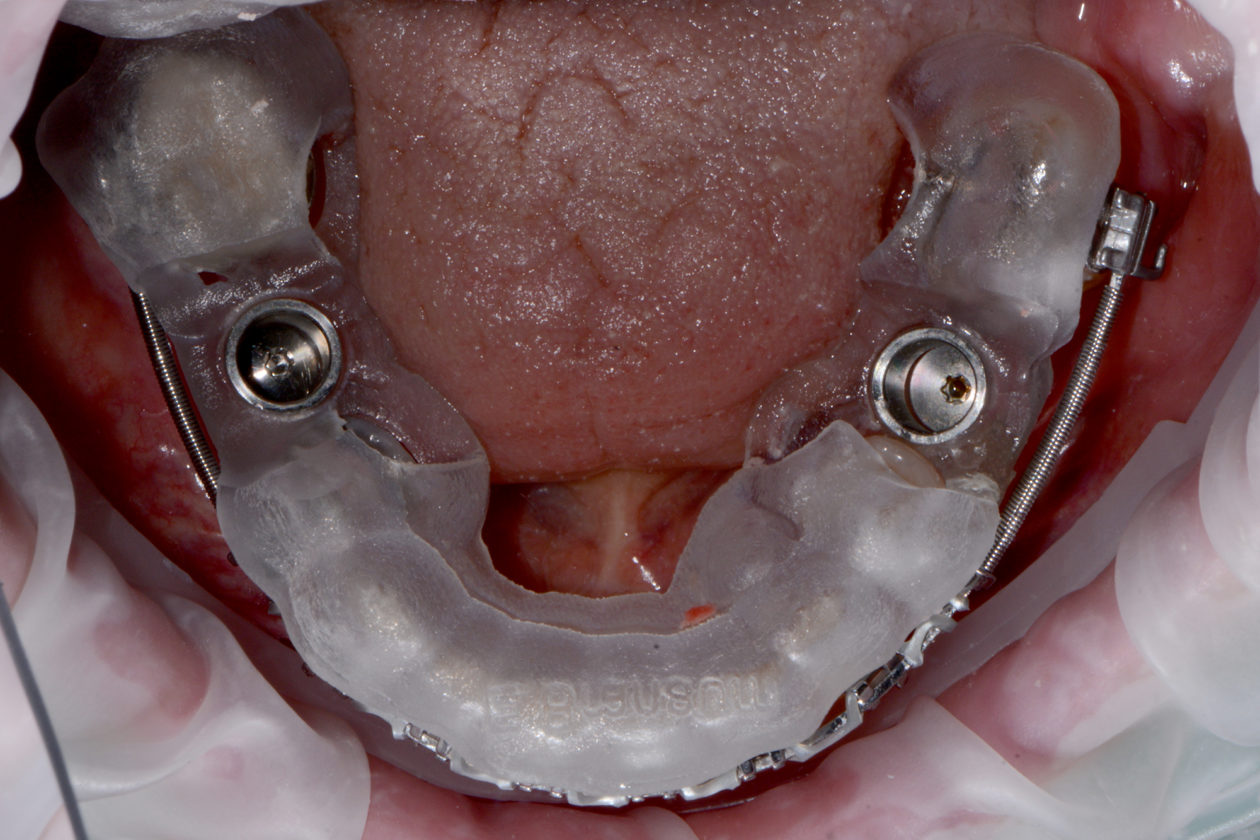

Our non-clinical goals in this case were to convey to the patient that her problems were an interdisciplinary, complex issue that had been ongoing and worsening for many years. Our solution to these problems would require the collaborative efforts of a team of dentists. The objective clinical goals were to orthodontically move her teeth into a less restrictive position and create room for restoration of lost tooth structure. Implants would be used not only to replace missing teeth but to provide orthodontic anchorage to facilitate movements that would not be possible with conventional orthodontics. Our final restorative goals were to reestablish ideal form and function, creating an occlusion that was stable and comfortable, enabling long term dental health. As her desires were specifically not to address esthetics, we were clear esthetic improvements were the result of correcting form and function. Of note is the fact that this case, from the restorative and surgical standpoint, was to be accomplished, with few small exceptions, entirely digitally.

In considering a treatment plan for our patient, it is important to note that in our initial information gathering she was clear she had no esthetic concerns. Further, her desires were single tooth in nature, specifically to replace her missing lower molar teeth. The most challenging aspect of this plan was communicating to the patient what her true problem was and having her accept that the problem, if left untreated, was a challenge to her dental health for life. She must also understand the solution to the problem and to appreciate that comprehensive care with orthodontics and restorative dentistry is to solve a long standing functional and structural problem. Esthetic improvements are a consequence of restorative and structural improvements, not a primary driver in the plan. In our multiple consultation appointments, we allowed the patient to ask as many questions as she needed answered. In short, it took her about six months to overcome the single tooth mindset that she had been taught by her previous dental experiences. Photographs were a significant component in our explanation. They demonstrated the excessive wear resulting in the extractions and were an indicator of what she should expect if she chose only to have the missing lower molars replaced. The orthodontic consultation was a key in her accepting care. An opinion from one of our specialist colleagues, another set of eyes if you will, added support for our recommendations. The plan ultimately accepted by the patient was altered from our originally proposed plan per the patient’s request to only restore the mandibular posterior teeth leaving the mandibular anterior teeth unrestored. With this compromise we still felt we could achieve acceptable anterior function. That altered our overall plan in two ways. First, the orthodontic plan would now not include intrusion of the lower anterior teeth as the incisal edges will dictate tooth position, not the gingival levels. The orthodontist would place the incisal edges of these teeth in ideal position. And second, when restoring the mandibular posteriors after placement of the maxillary restorations, we will not alter the VDO.